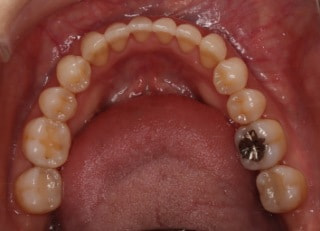

治療後パノラマレントゲン

歯根のパラレリングは良好です。顎関節に問題はありません。